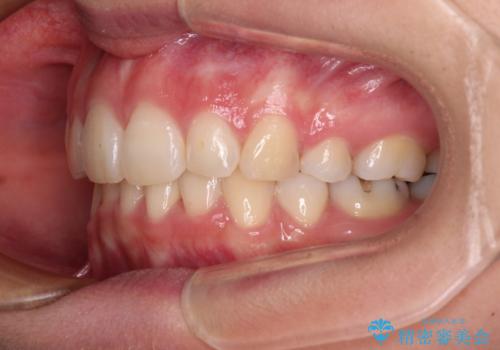

デコボコで飛び出した前歯 ワイヤー装置による抜歯矯正

- 上下前歯のデコボコと、飛び出した前歯を気にして来院された患者様です。

口元を積極的に引っ込めるために、上下左右の小臼歯計4本を抜歯することとしました。

矯正治療前の咬み合わせで、前歯がすり減ってしまい、歯列が整ったときに先端がガタガタになってしまったため、矯正治療後に形態修正を行いました。